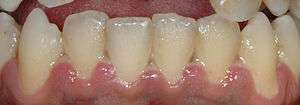

Mild presentation of ANUG on the gums of the lower front teeth

Common marginal gingivitis in response to subgingival plaque is usually a painless condition. However, an acute form of gingivitis/periodontitis, termed acute necrotizing ulcerative gingivitis (ANUG), can develop, often suddenly. It is associated with severe periodontal pain, bleeding gums, "punched out" ulceration, loss of the interdental papillae, and possibly also halitosis (bad breath) and a bad taste. Predisposing factors include poor oral hygiene, smoking, malnutrition, psychological stress, and immunosuppression.[20]:97–98 This condition is not contagious, but multiple cases may simultaneously occur in populations who share the same risk factors (such as students in a dormitory during a period of examination).[23] ANUG is treated over several visits, first with debridement of the necrotic gingiva, homecare with hydrogen peroxide mouthwash, analgesics and, when the pain has subsided sufficiently, cleaning below the gumline, both professionally and at home. Antibiotics are not indicated in ANUG management unless there is underlying systemic disease.[20]:437–438